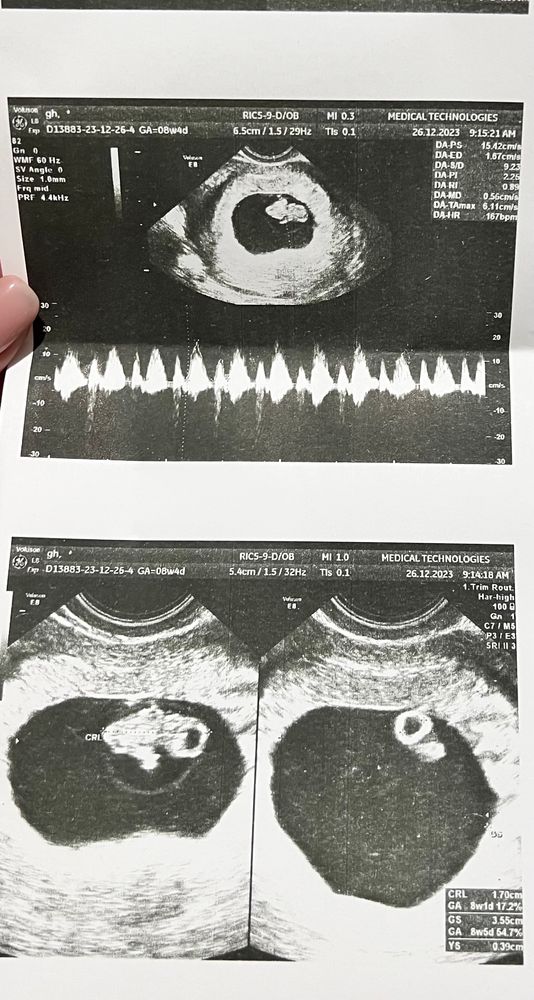

УЗИ 8 недель 1 день

Сегодня сходила опять на УЗИ для своего спокойствия. Подрос малышок. КТР 18 мм ( + 10мм за 10 дней). Сердцебиение ритмичное❤️. Жм 4 мм. Двигался, наверное, волновался вместе со мной.

Локализация хориона по передней стенке матки, а на прошлом УЗИ по задней. Такое может быть?

Через 8 дней записана на след УЗИ.